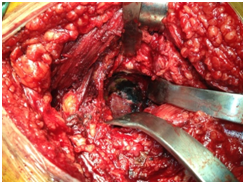

After the postoperative recovery of the patient, we scheduled the total arthroplasty in the right hip, which was performed 3 months after the previous operation on the knee, with great success in both cases (Figures 8 & 9). Six months later, the total left knee arthroplasty was performed, being also successful (Figure 10). It is extremely rare for a patient suffering from alkaptonuria to be subjected to three total arthroplasties with the syndrome not being preoperatively diagnosed. From this fact, emerges the great clinical significance of this case.

Figure 9 Total hip arthroplasty. The characteristic dark pigmentation of the femoral head and the acetabulum.